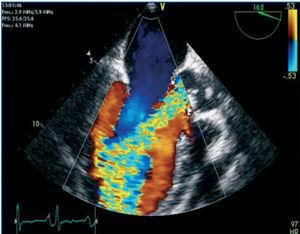

A cardiac ultrasound was performed, showing massive aortic regurgitation (AR) with a preserved left ventricular ejection fraction (LVEF) (69%). Three vegetations were found in the aortic valve, and the largest one measured 20mm. A pericardial haemorrhage was also observed without signs of heart block or thrombi (Figures 1 and 2).

Figure 2. Large vegetation adhered to the right coronary sigmoid